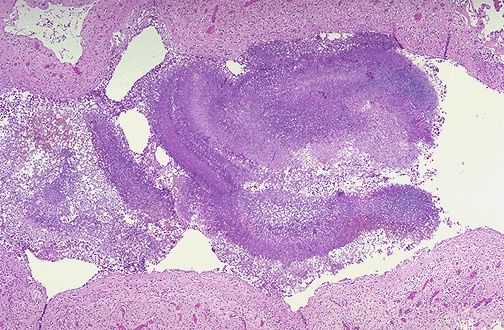

A fungus ball composed of blue-staining hyphal elements of Aspergillus is seen here in a bronchus. Fungus balls may also form when fungi colonize cavitary lesions of tuberculosis.